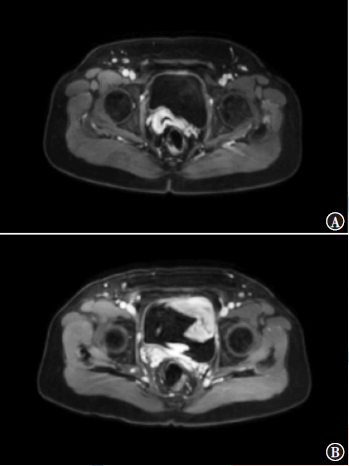

盐酸安罗替尼为多靶点小分子酪氨酸激酶抑制剂,可作用于肿瘤新生血管,并诱导肿瘤细胞凋亡,其广泛应用于肾细胞癌、结直肠癌、肝癌等肿瘤的治疗。本例应用放化疗联合盐酸安罗替尼治疗复发性子宫内膜癌患者,取得满意的疗效。